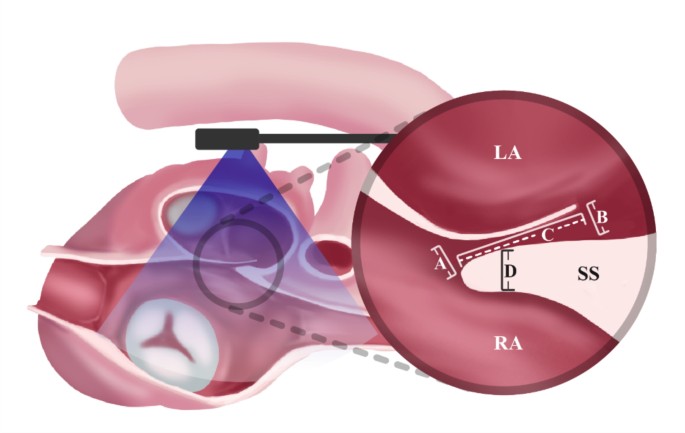

TEE is the gold standard for evaluating the anatomical features of PFO. The anatomical data of all patients were measured using TEE before the percutaneous intervention. The measurements included opening size on the left atrial aspect, opening size on the right atrial aspect, tunnel length and thickness of secondary septum, as well as the presence of comorbid ASA, Eustachian valve, Chiari network, and atrial septal defects. ASA was defined as a localized outpouching of the interatrial septum with a protrusion of more than 10 mm beyond the plane of the atrial septum, observed either towards the right atrium or the left atrium, or exhibiting bidirectional movement. The measurement methods are shown in Fig. 3. The PFO anatomical data of all patients were measured by the same experienced sonographer using the same TEE instrument (model no.: ACUSON NX3 Elite, Siemens Medical Solutions, Issaquah, WA, USA).

Measurements made in the TEE mid-esophageal bicaval view (90–120°): (A) Size of right atrial opening: the widest distance between the primary septum and secondary septum was measured perpendicular to the interatrial septal plane. (B) Size of left atrial opening: the widest distance between the primary septum and secondary septum was measured perpendicular to the interatrial septal plane. (C) Tunnel length: the length of overlap between the primary septum and secondary septum was measured parallel to the interatrial septal plane. (D) Secondary septum thickness: the width of the thickest point on the middle to lower segment of the secondary septum was measured perpendicular to the secondary septum. PFO, Patent foramen ovale; LA, Left Atrium; RA, Right Atrium; SS, Secondary septum.